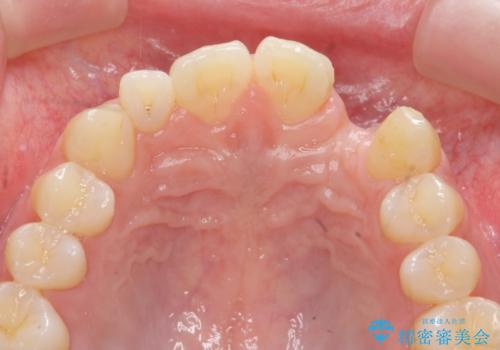

前歯部 インプラント治療

それぞれの治療に特徴がありますが、取り外しの必要がなく隣の歯を削る必要も必要ないインプラント治療を選択されました。

- 55万円(ストローマンインプラント・ジルコニアカスタムアバットメント・骨造成・仮歯・ジルコニアクラウン)費用は治療当時の料金となります

前歯部にインプラントを埋入し、きれいに仕上げるためには骨の造成技術や歯肉の厚みを増すような処置を行い、インプラント周囲の環境を整備することが肝要です。